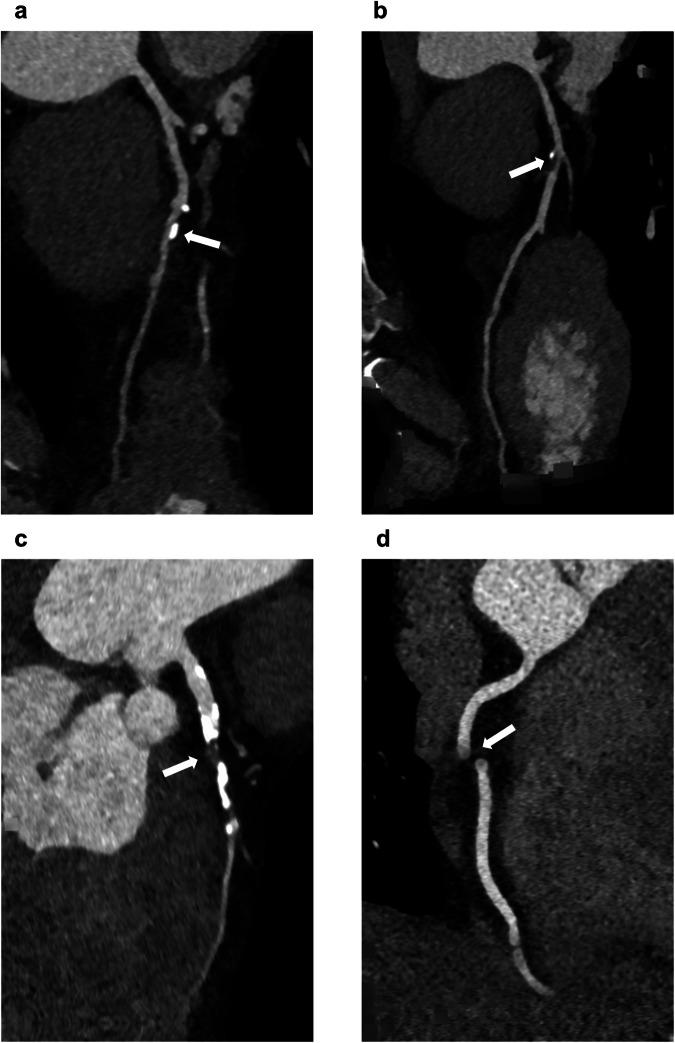

使用更新的深度学习模型从冠状动脉计算机断层扫描血管造影扫描中自动分类冠状动脉病变:ALERT研究。

Automated classification of coronary LEsions fRom coronary computed Tomography angiography scans with an updated deep learning model: ALERT study.

The use of deep learning models for quantitative measurements on coronary computed tomography angiography (CCTA) may reduce inter-reader variability and increase efficiency in clinical reporting. This study aimed to investigate the diagnostic performance of a recently updated deep learning model (CorEx-2.0) for quantifying coronary stenosis, compared separately with two expert CCTA readers as references.

Overall, 50 patients and 150 vessels were evaluated. Inter-reader agreement using the binary classification at patient level was 91.8% (45/49) with a Cohen's kappa of 0.80. For the 6-group classification at vessel level, inter-reader agreement was 67.6% (100/148) with a linearly weighted kappa of 0.77. CorEx-2.0 showed 100% sensitivity for detecting CAD-RADS ≥ 4 and kappa values of 0.86 versus both readers using the binary classification at patient level. For the 6-group classification at vessel level, CorEx-2.0 demonstrated weighted kappa values of 0.71 versus reader 1 and 0.73 versus reader 2.

CorEx-2.0 identified all patients with severe stenosis (CAD-RADS ≥ 4) compared with expert readers and approached expert reader performance at vessel level (weighted kappa > 0.70).

Question Can deep learning models improve objectivity in coronary stenosis grading and reporting as coronary CT angiography (CTA) workloads rise? Findings The deep learning model (CorEx-2.0) identified all patients with severe stenoses when compared with expert readers and approached expert reader performance at vessel level. Clinical relevance CorEx-2.0 is a reliable tool for identifying patients with severe stenoses (≥ 70%), underscoring the potential of using this deep learning model to prioritize coronary CTA reading by flagging patients at risk of severe obstructive coronary artery disease.